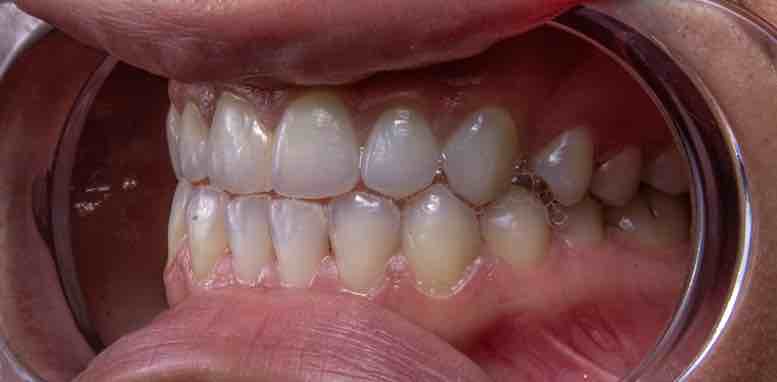

加齢や歯周病によって歯ぐきが下がると、歯と歯の間に三角形の隙間(ブラックトライアングル)ができます。この隙間は食べ物が入り込みやすく、噛むたびに繰り返し押し込まれることで炎症も起こしやすくなります。

一方で、歯が隣の歯と接触自体はあるものの、接触がズレている場合も、食べ物は挟まりやすくなります。これは、歯の接触点が“理想の位置”からずれているため、歯と歯の間に連続した壁が作られず、食べ物が逃げる隙間ができてしまう状態です。少し斜めに傾いた歯や、歯列の微小な変化によって、噛んだときに食べ物がその隙間に押し込まれてしまいます。